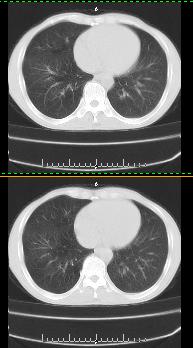

以下是引用liaoqiang在2008-3-21 17:45:00的发言:[br]右上叶尖段、后段有多发小结节和小条状影。考虑感染(结核可能性大。)。建议治疗后复查。

以下是引用王2008在2008-3-21 17:38:00的发言:[br]右上叶后段沿纹理走向呈串珠状.边缘欠清密度增高影,局部胸膜增厚.[br]考虑1.右上支扩可能.2.右上炎症.建议治疗后复查.请各位老师指教.

以下是引用lj11119999在2008-3-21 18:15:00的发言:[br]右上叶尖段、后段有多发小结节和小条状影。考虑感染(结核可能)建议进一步检查!